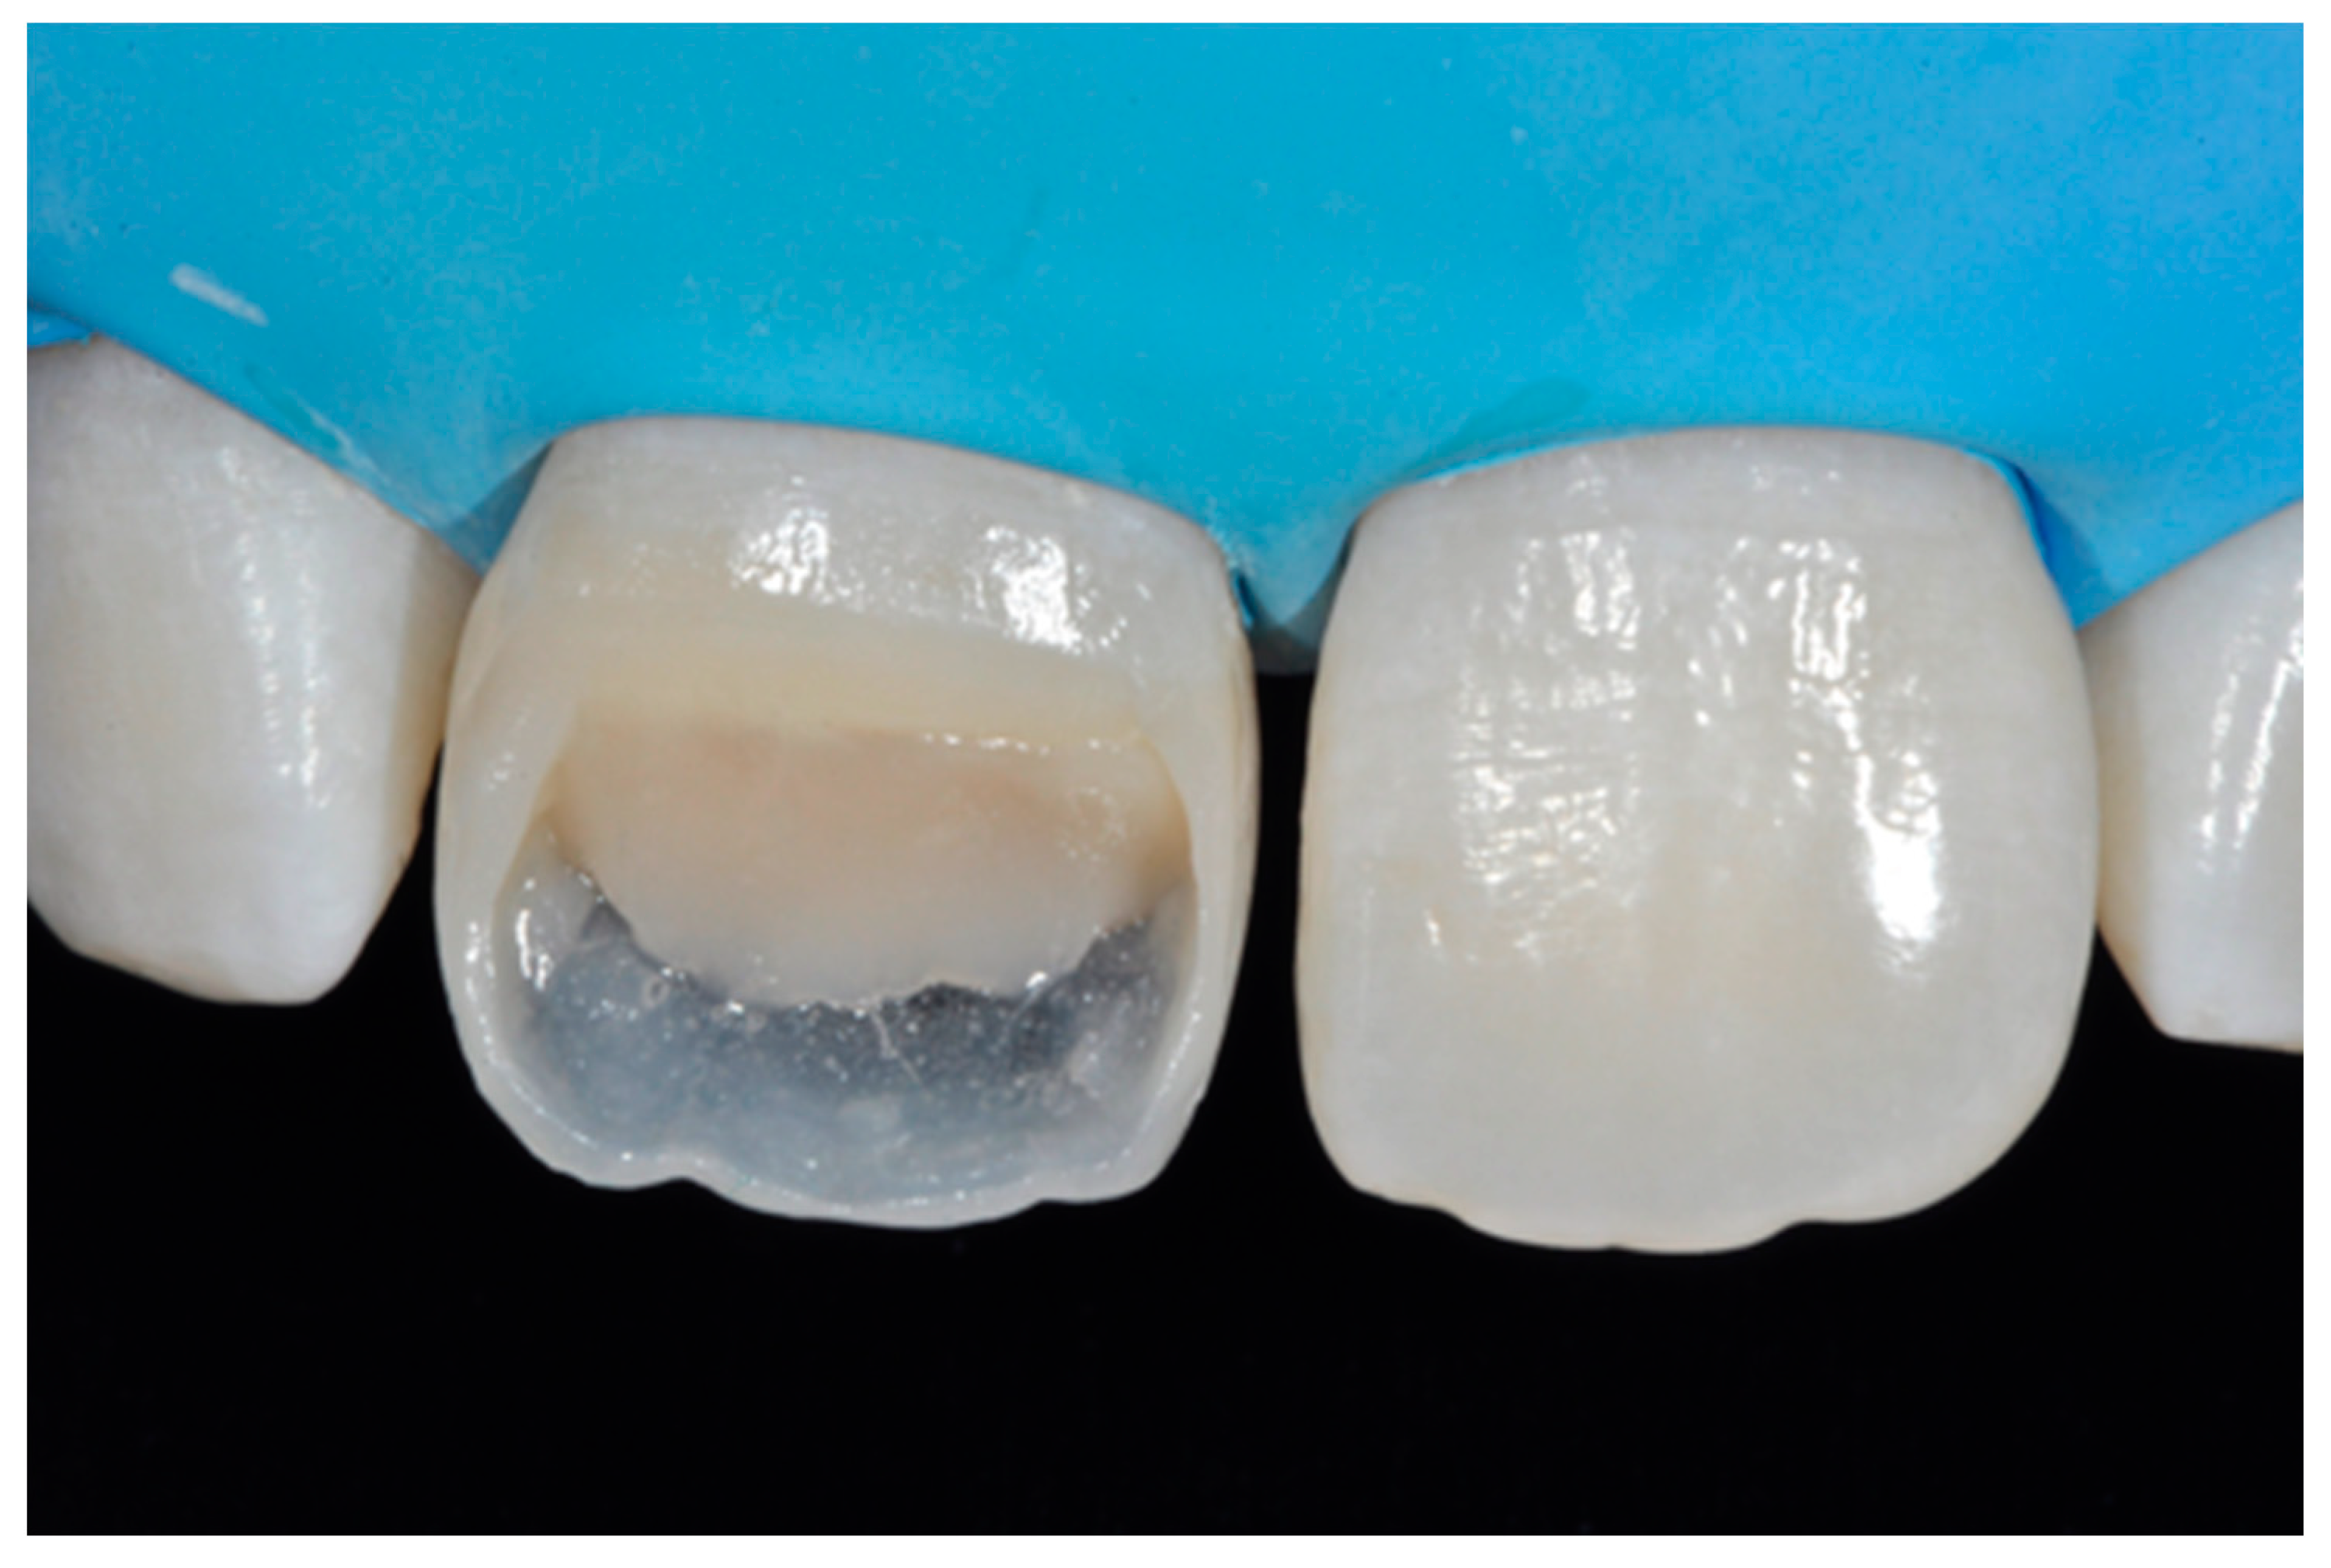

2.1.3. Completion of the Layering Procedure, Finishing and Polishing

A single shade of dentin (Clearfil Majesty ES-2, A1D, Kuraray Noritake Dental, Tokyo, Japan) was then applied placing separate increments (Figure 10 and Figure 11) to build the dentinal body, leaving space for incisal translucencies. The translucent shade (Clearfil Majesty ES-2, A1E, Kuraray Noritake Dental, Tokyo, Japan) was then applied to complete the restoration (Figure 12).

Figure 10.

First increment of the dentinal body. Reprinted from Restauri diretti nei settori anteriori, G. Paolone, S. Scolavino, © 2021, with permission from Quintessence Publishing Italy.

Figure 11.

Dentinal body completed. Reprinted from Restauri diretti nei settori anteriori, G. Paolone, S. Scolavino, © 2021, with permission from Quintessence Publishing Italy.

Figure 12.

Enamel layer applied. Reprinted from Restauri diretti nei settori anteriori, G. Paolone, S. Scolavino, © 2021, with permission from Quintessence Publishing Italy.